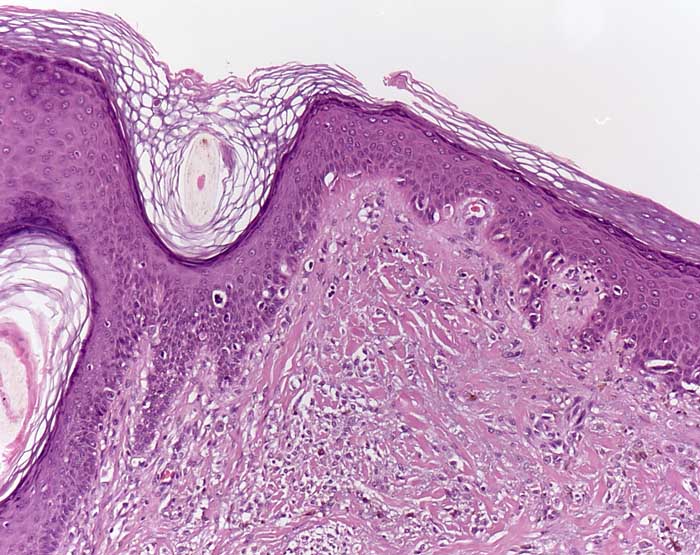

Desmoplastisches Melanom (Lentigo maligna Melanom)

Lentiginöse Hyperplasie atypischer Melanozyten entlang der Junktionszone entsprechend einer Lentigo maligna. Die angrenzende Dermis ist narbenartig fibrosiert und ist auffallend zellreich (desmoplastisches Melanom). Die dermalen Zellen weisen lediglich geringe Atypien auf.

Histologie

100